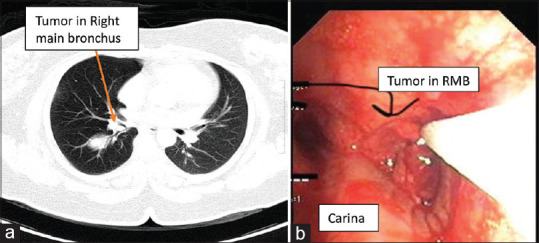

Abstract: Adult patients with central airway tumors commonly present with dyspnea on exertion. These patients may remain asymptomatic until more than half of the airway diameter is obliterated. Anesthesia for debulking a central airway tumor is challenging. Anesthetic management should include a strategy for oxygenation and ventilation, a plan for the same if tumor bleeding aggravates airway obstruction and a plan to deal with acute emergencies like pneumothorax and cardiac arrest. Patients with airway tumors occupying < 50% airway diameter and comfortable during routine activities can be managed using relaxant anesthesia and rigid bronchoscopy for debulking. Airway tumors with >75% airway lumen compromise are the sickest and may present in respiratory failure. We found that in these patients, maintaining spontaneous ventilation, avoidance of general anesthesia, and muscle relaxation are the keys to management. General anesthesia and muscle relaxants decreases / abolishes negative intrapleural pressure, which may result in dynamic hyperinflation and pneumothorax in presence of airway obstruction. In this subset, we routinely use i-gel (sizes 4 and 5) as an airway conduit for debulking. We prefer i-gel® (Intersurgical Ltd, UK) over rigid bronchoscopy as it requires less sedation. To allow this, it is prudent to ensure excellent airway anesthesia prior to i-gel placement using airway blocks, topical anesthetics, and titrated doses of sedation. We manage 20-30 cases of central airway tumors for debulking or stenting every year and share our experience of managing four cases depicting a spectrum of airway and review the literature on anesthetic management of central airway tumors.